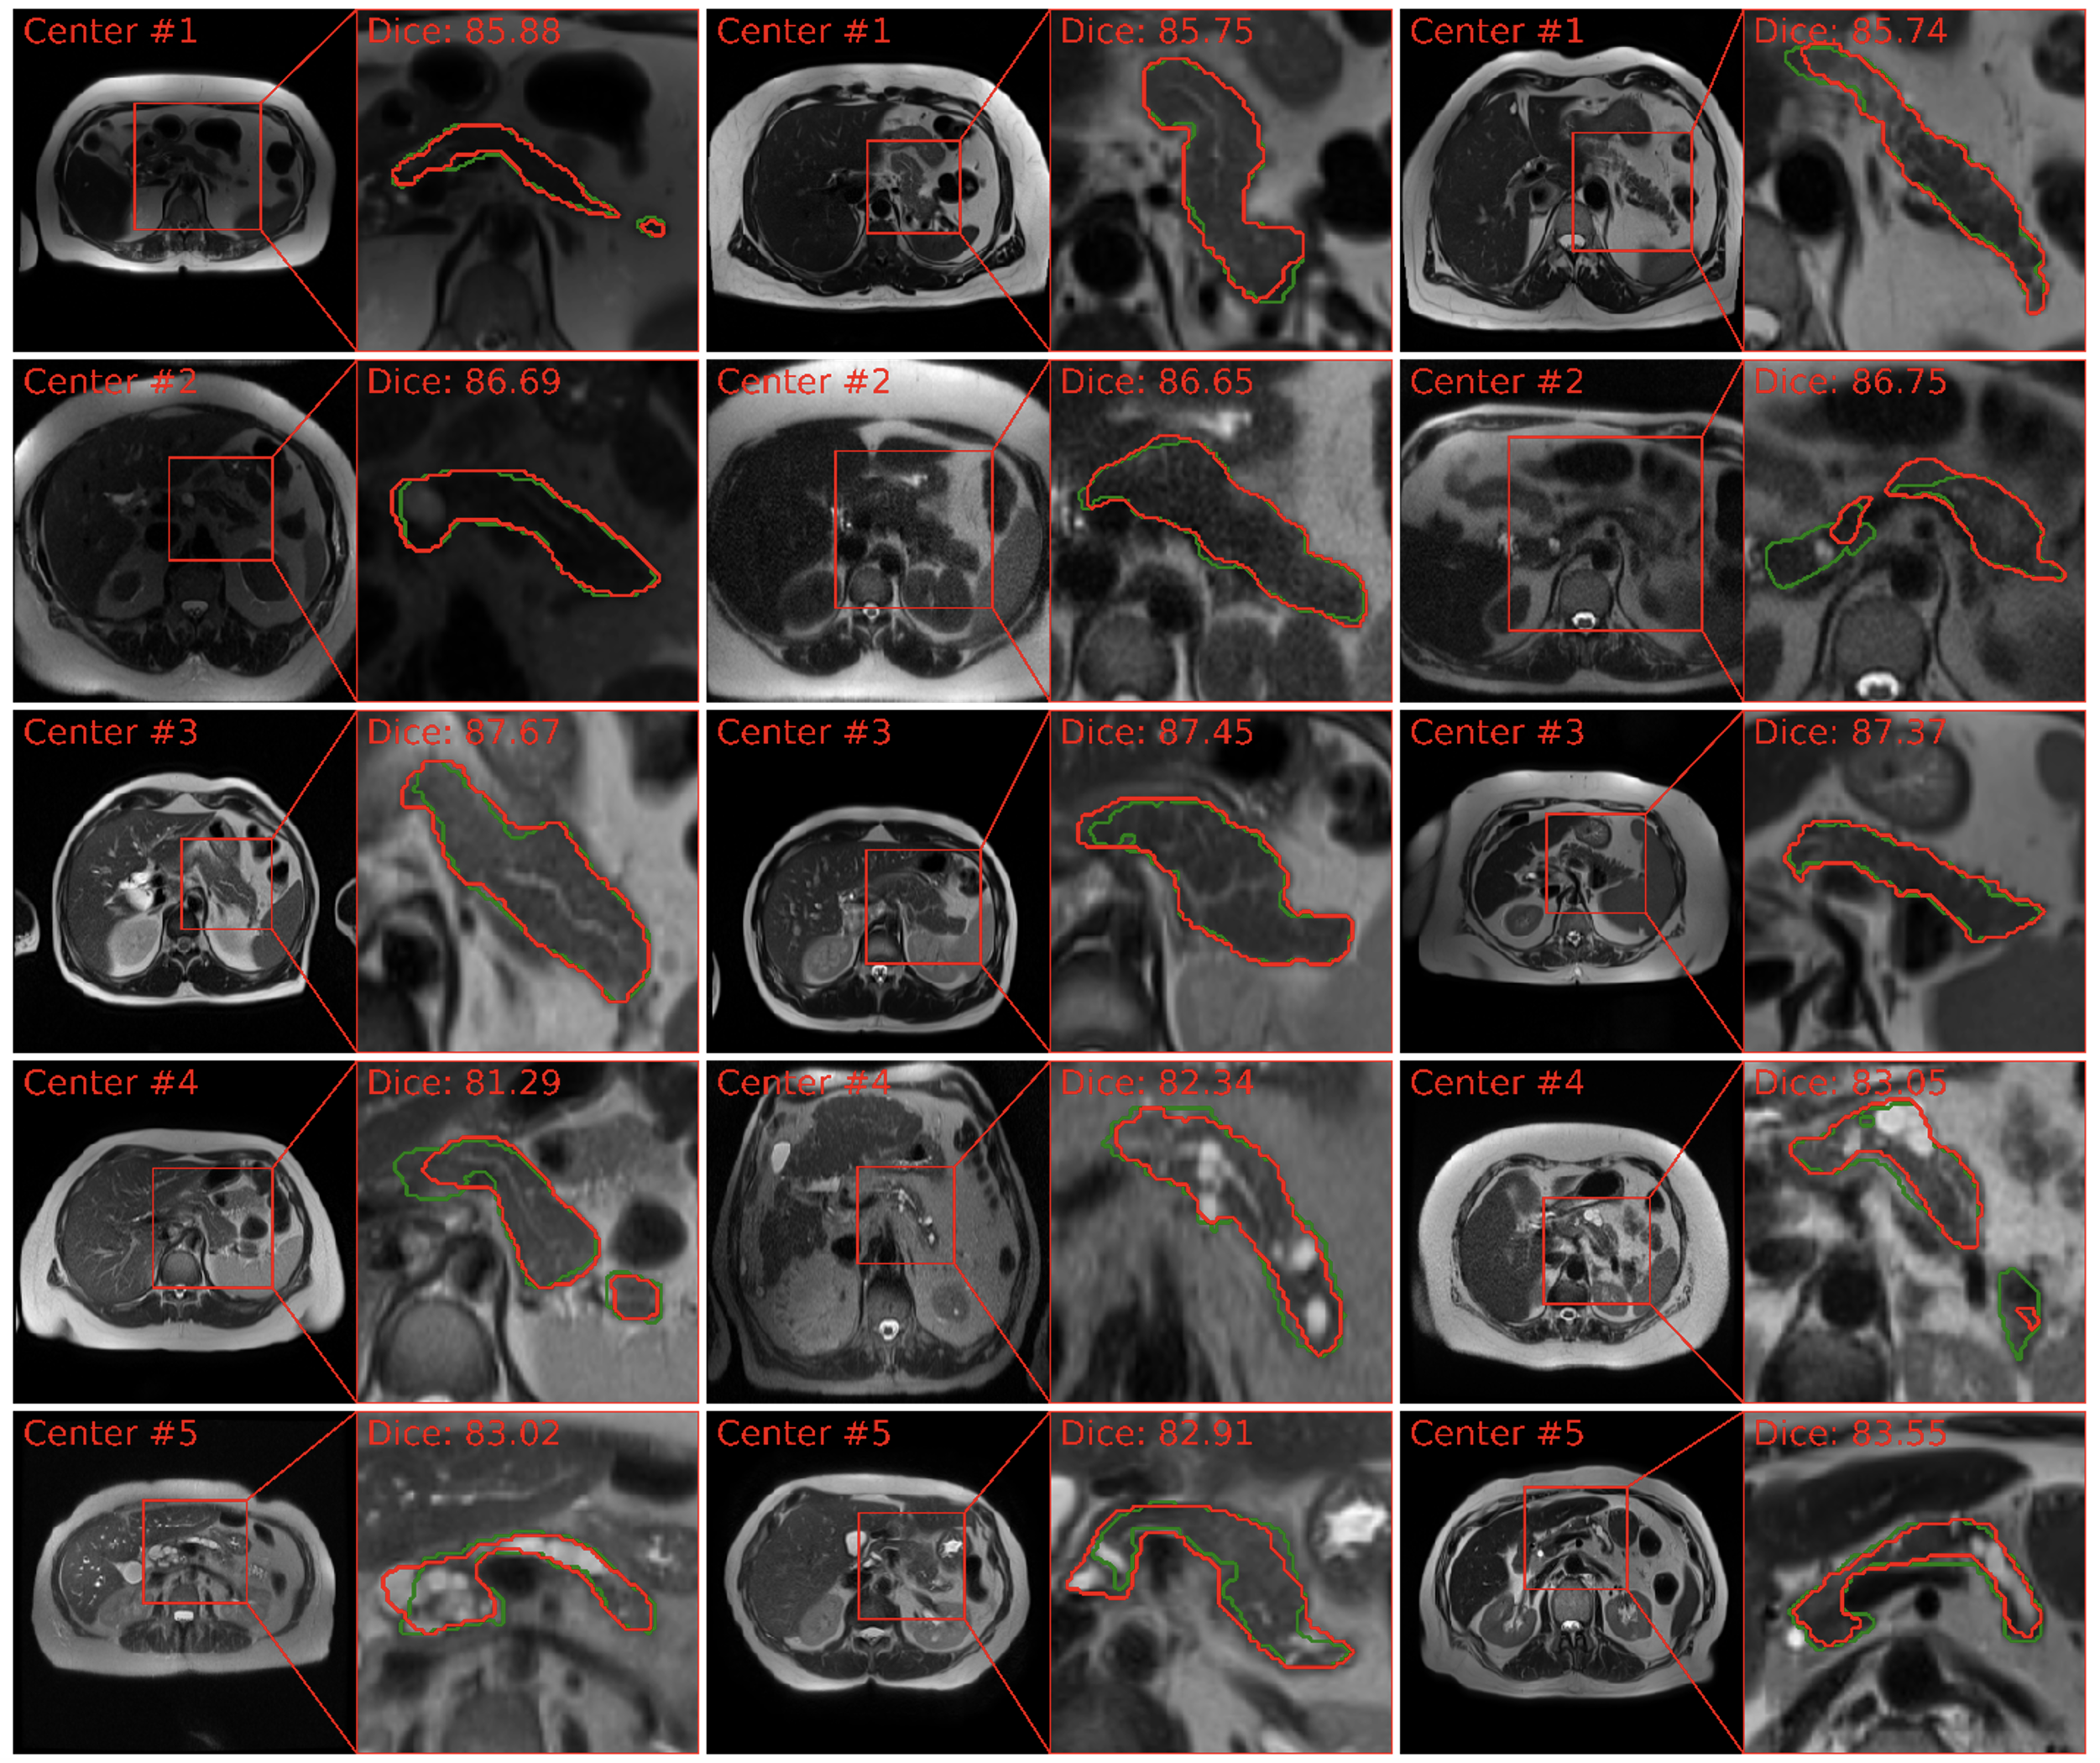

For T1W MRI segmentation, PanSegNet exhibited noteworthy performance within the source domain, achieving average Dice scores of 85.02% (±7.90%, median 87.26%) with HD95 distance of 6.37 mm (± 7.96, median 4.40 mm). Specifically, within the Center#1 and Center#2 datasets, our model achieved an average Dice coefficient of 86.44% (±7.04, median: 88.89%) and 83.70% (±8.41%, median: 86.01) (Table 4). Our results exhibit the model’s proficiency in accurately delineating pancreatic structures within the T1W modality. This strong segmentation capability was further visually validated through our segmentation results in Figure 5, which closely aligned with ground truth annotations.

Refer to caption

Fig. 5: MRI T1W pancreas segmentation visualization across various data centers. The segmentation delineations illustrate the model’s capability to delineate pancreas boundaries precisely, exemplified by the accurate results. We observe domain shifts in external validation from Centers #3, #4, and #5.

We also observed domain-shift in segmentation performance when conducted external validation. The Dice scores decreased to 81.55% (-4.08%, p-value: 1.92×10-2), 79.80% (-6.13%, p-value: 7.96×10-3), and 76.21% (-10.36%, p-value: 2.04×10-8), respectively, for data from three different centers. We also performed experiments with the publicly available AMOS dataset as it includes 40 MRI scans for pancreas, and the Dice score also dropped to 81.14% (-4.56%, p-value: 8.44×10-3). While these reductions highlight the challenges posed by domain shifts, it is worth noting that our model still maintained a strong performance even in these cross-domain scenarios.

4.3.2 T2W MRI

Our PanSegNet similarly demonstrated strong segmentation capabilities on T2W sequences. Within the source domain (Center#1 and Center#2 datasets), the model achieved an average Dice coefficient of 86.27% with a standard deviation of 6.44% (median: 87.84%). When assessing the segmentation performance in the Center#3 dataset, we observed a considerably high Dice coefficient of 87.83% (±1.80%, median 89.22%). When deploying the model in out-of-distribution settings (Center#3 and Center#5), the Dice coefficients were decreased to 81.41% (-5.63%, p-value: 4.23×10-4) and 83.03% (-3.76%, p-value: 1.79×10-2), respectively, implying the impact of domain shifts. Despite the shifts, the results are still at the forefront of current advancement. Visual results are illustrated in Figure 6, which closely aligned with ground truth annotations.

Fig. 6: MRI T2W pancreas segmentation visualization across various data centers. The segmentation delineations illustrate the model’s capability to delineate pancreas boundaries precisely, exemplified by the accurate results. The Center #3 T2W segmentation also exhibits relatively high results, showcasing its segmentation potential. We observe domain shifts in external validation from Centers #3, #4, and #5.